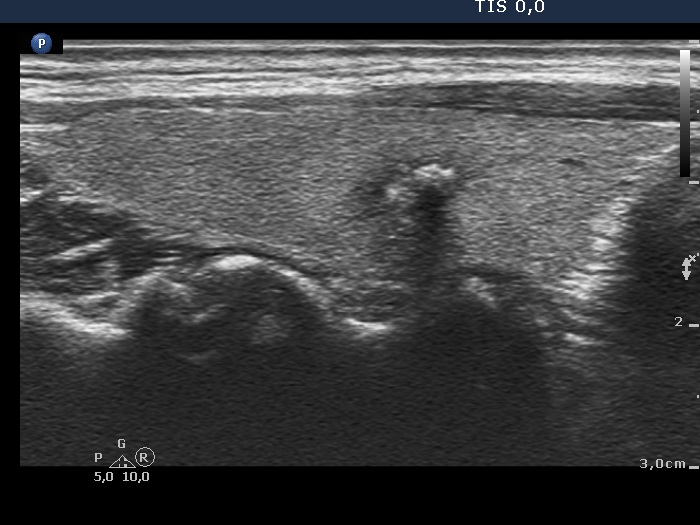

The borders of the nodule - case 2166 (ultrasonographic picture 3)

Right lobe, longitudinal view, enlargement.